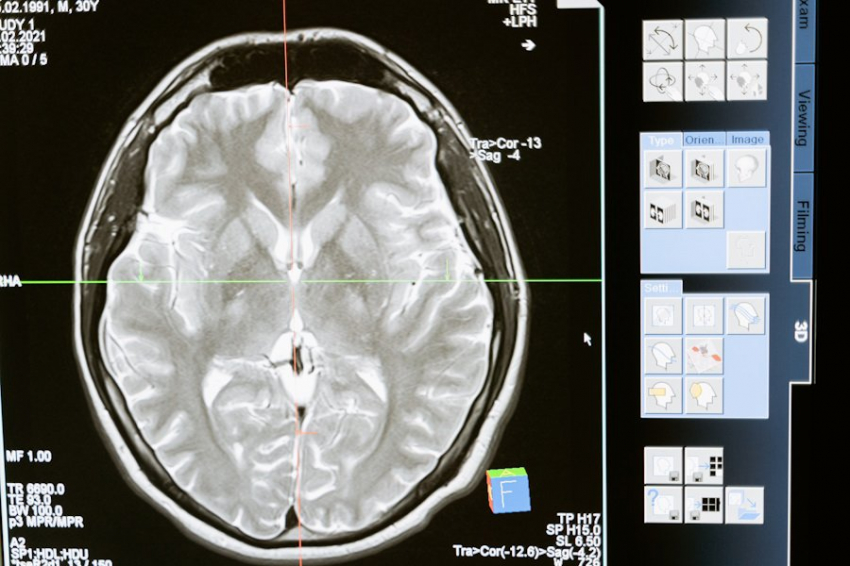

Фото из открытых источников

Российские учёные сделали важный шаг в борьбе с одной из самых агрессивных форм рака мозга — глиобластомой. Команда исследователей нашла комбинации молекул-аптамеров, которые значительно снижают способность опухолевых клеток к делению и распространению. Это открытие может привести к созданию новых, более эффективных препаратов против глиомы, сообщает RT.

Глиобластома — это злокачественная опухоль, которая часто оказывается устойчивой к лечению. Препятствия на пути к её терапии включают сложность хирургического удаления, низкую эффективность химиотерапии из-за гематоэнцефалического барьера, а также высокий риск рецидивов.